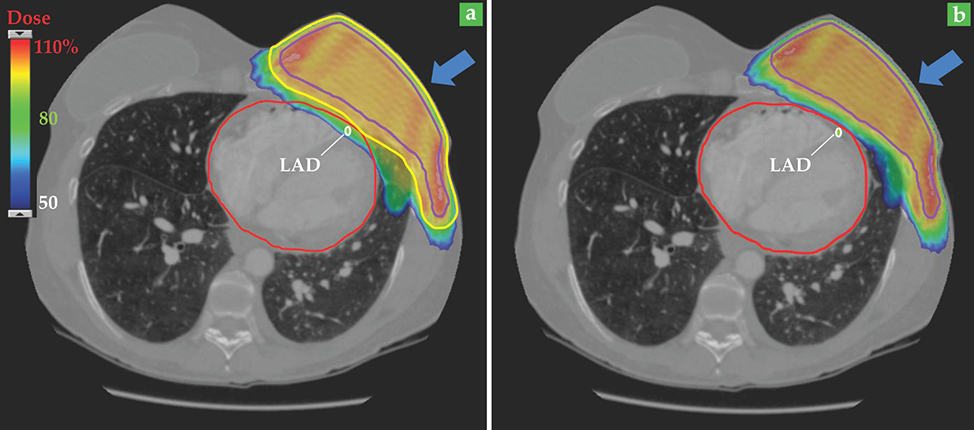

As an example, figure 5 illustrates the distribution of dose delivered to a patient receiving proton radiotherapy for breast cancer. For a standard treatment (figure 5a), the volume that receives the full treatment dose, enclosed by the yellow line, includes the target volume to be treated for cancer (enclosed by the purple line) plus the extra margin to account for beam-range uncertainty. As figure 5b shows, the dose delivered to the heart and lung can be significantly decreased if the range uncertainty margin can be reduced or even eliminated through daily in vivo range imaging. In that case, only the desired treatment volume would receive the full treatment dose. Of particular importance is a large reduction in dose to the left anterior descending coronary artery (LAD; shown in white in the

Figure 5. Patient outcomes can be greatly improved by in vivo imaging that reduces beam-range uncertainty by just a few millimeters. In this breast cancer patient, the intended treatment volume is indicated by the purple line, and the direction of the treatment beam is shown by the blue arrow. (a) To account for the beam-range uncertainty, the treatment volume must be expanded to the region enclosed in yellow. As a result, significant dose (shown here as a percentage of the prescribed dose) is delivered to the heart (red line) and the left anterior descending coronary artery (LAD; white line). (b) With range-verified proton radiotherapy, no expansion to the treatment volume would be needed. Dose delivered to the heart and the LAD is greatly reduced, as is the patient’s risk of radiation-induced heart disease.